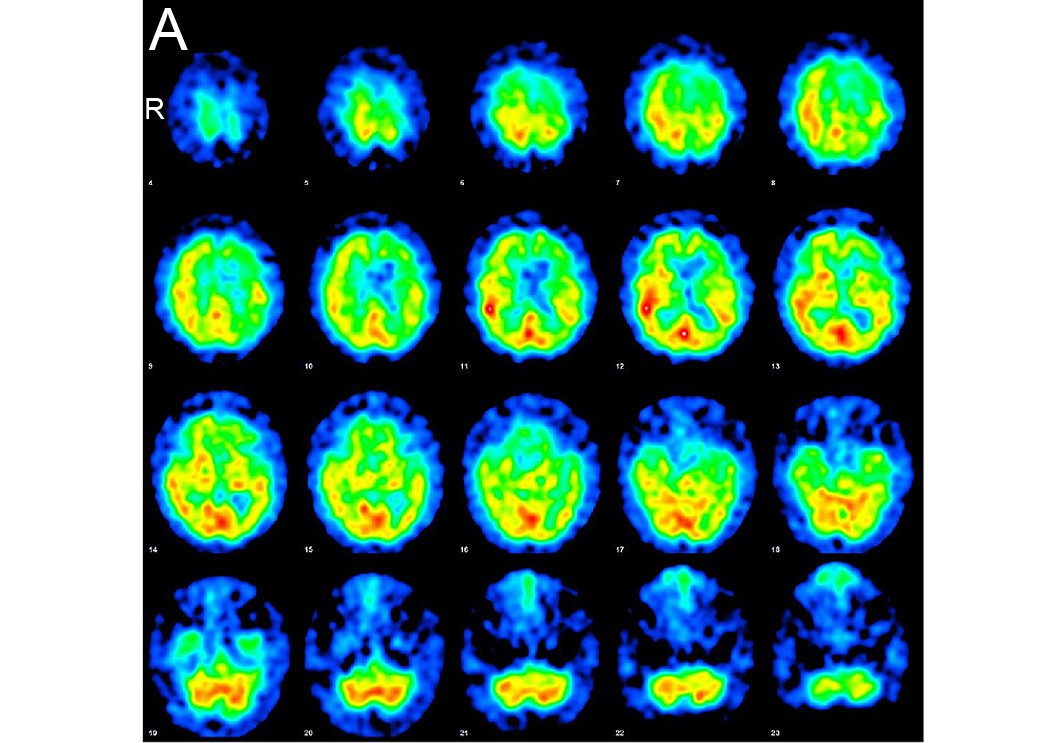

若月 里江, 武内 智康, 岡 耕太, 竹ノ内 晃之, 渡邊 一樹, 中村 友彦

Rie Wakatsuki, Tomoyasu Bunai, Kouta Oka, Akiyuki Takenouchi, Kazuki Watanabe, Tomohiko Nakamura